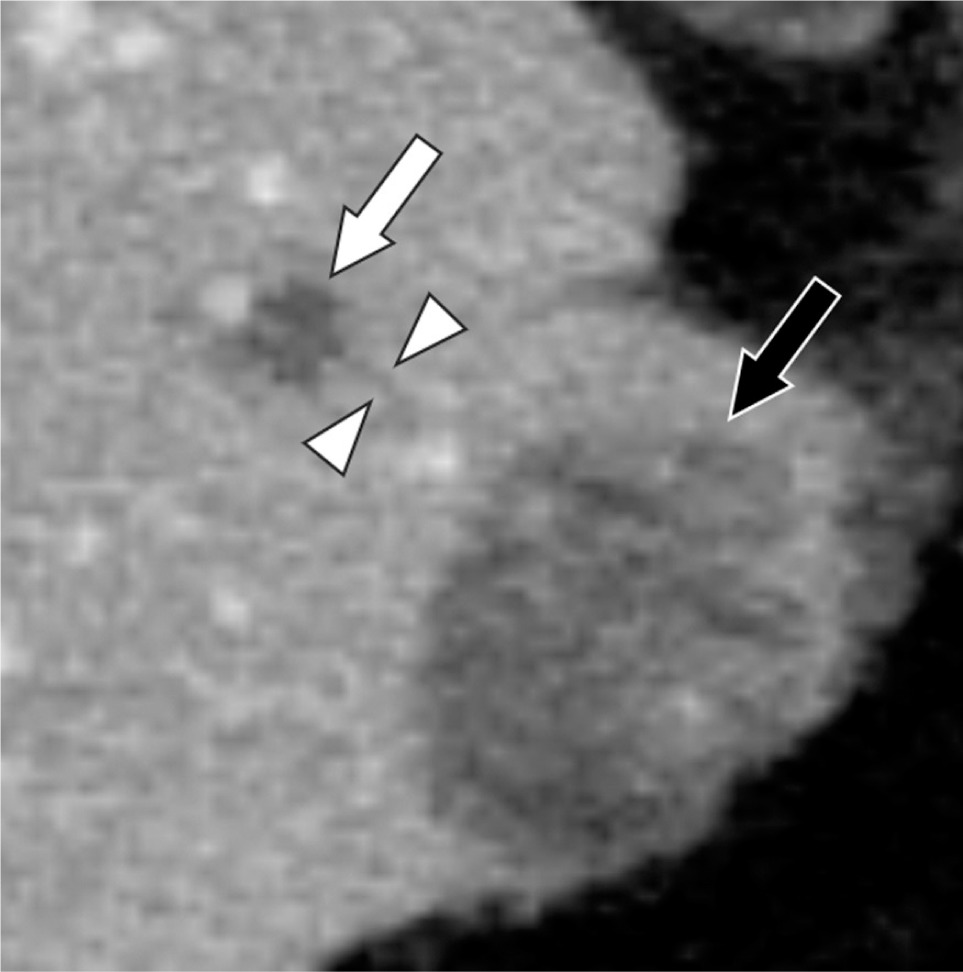

In percutaneous CRA of 223 liver tumors in 135 patients, Sainani et al. reported that the incidence of portal and hepatic venous thrombosis after ablation was 24% (54/233): these included 49 thromboses in portal vein branches, 4 in branches of both portal and hepatic veins, and 1 in a hepatic vein branch (6). The thrombosed veins were outside but adjacent to the ablation zone in 36 patients (66.7%) and within the ablation zone in 18 patients (33.3%) (6). They speculated that one mechanism of thrombus formation outside the ablation zone is thrombosis resulting from freezing within the ice-ball but outside the lethal isotherm, citing the results of Littrup et al. (7). In our patient, no portal venous thrombus was in contact with the ablation zone; however, there was a small portal vein thrombus near the ablation zone (Figure 3). There may have been a subvisible thrombus contiguous with the ablation zone.

Figure 3: Axial contrast-enhanced CT 2 days after cryoablation reveals a small portal venous thrombus (arrowheads) adjacent to the subsegmental portal venous thrombus (white arrow) toward the ablation zone. There is no continuity between the small thrombus and the ablation zone (black arrow).